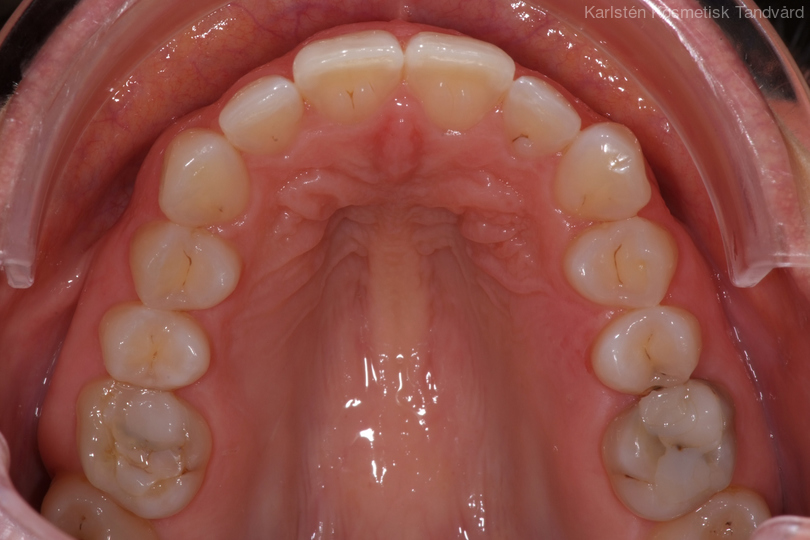

Tandreglering 4

40-årig kvinna som tycker att de två framtänderna står ut framför alla andra tänder. Behandlingen bestod av 11 månader med genomskinliga Invisalignskenor.